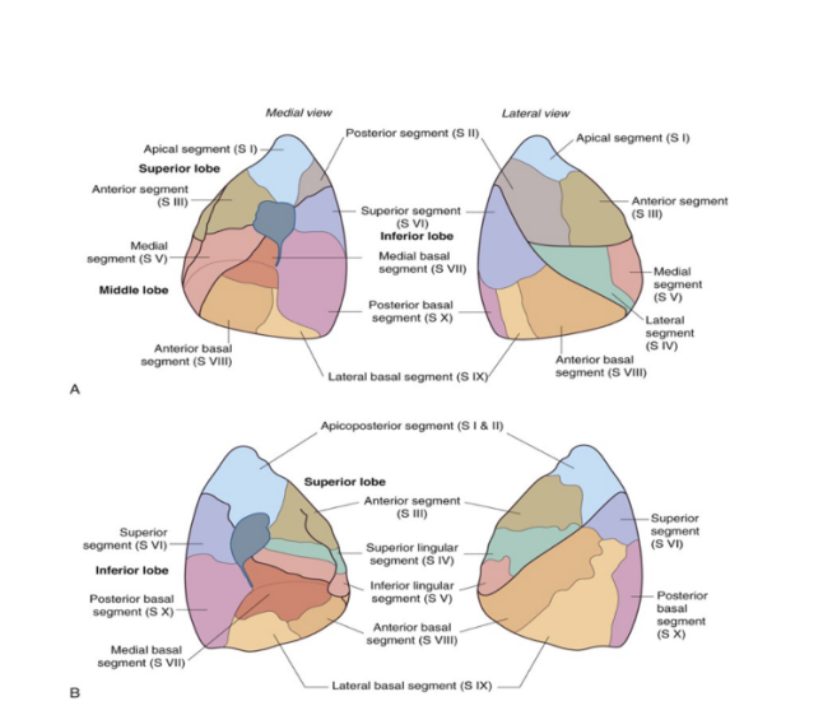

Lung/bronchopulmonary segments

Pyramidally shaped & are the largest subdivisions of a lobe with several important properties —

Apices face the lung root with their bases facing the pleural surface

Separated from adjacent segments by connective tissue septa

Supplied independently by a segmental bronchus & a tertiary branch of the pulmonary artery

Named according to segmental bronchi supplying them

Drained by intersegmental parts of the pulmonary veins lying in connective tissue between & drain adjacent segments

Can usually find 18-20 segments —

10 in right lung, 8-10 in left — dependent on combining of segments

Surgically resectable